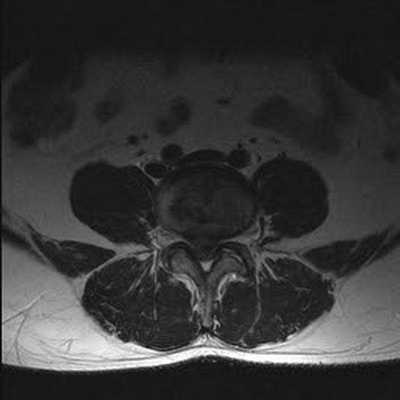

Стеноз позвоночного канала поясничного отдела на снимке МРТ

Стеноз позвоночного канала поясничного отдела на снимке МРТ (Т1 взвешенное изображение)